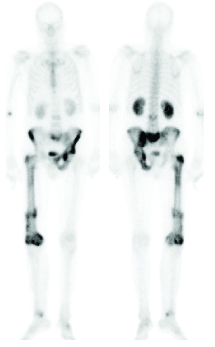

Widespread skeletal metastases in patient with prostate carcinoma.

bone scan

5. Metastatic Bone Disease.

Bone scanning is well established as the most sensitive technique for diagnosing metastatic bone disease and following progression. False negative bone scans occur in less than 2% of cases. Bone scans, however, are not always specific and X-ray examination of suspicious sites (scan directed) may be needed. X-rays are performed to see if there is an alternative, benign explanation for the bone scan abnormality. The presence of an abnormal scan with a normal X-ray

is highly suspicious

for metastasis.